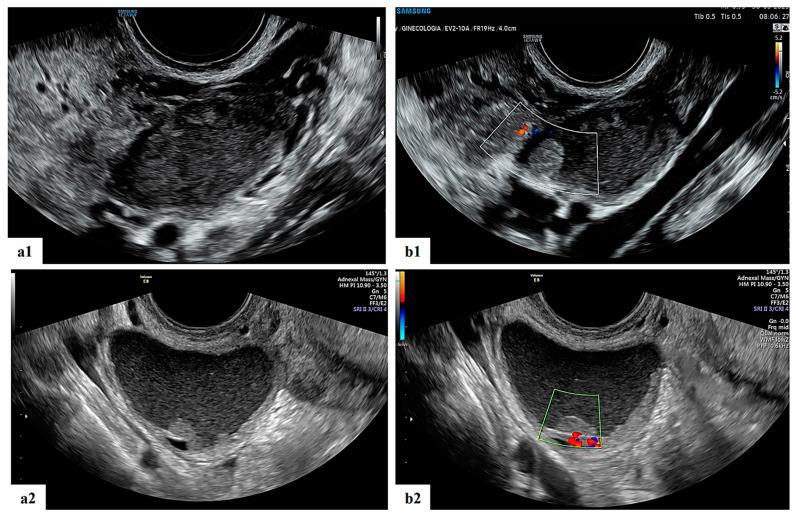

孕期诊断为卵巢肿物患者的超声特征及临床结局:单妇科超声中心的经验

Ultrasound Features and Clinical Outcome of Patients with Ovarian Masses Diagnosed during Pregnancy: Experience of Single Gynecological Ultrasound Center.

(1) Background: The number of adnexal masses detected during pregnancy has increased due to the use of first-trimester screening and increasingly advanced maternal age. Despite their low risk of malignancy, other risks associated with these masses include torsion, rupture and labor obstruction. Correct diagnosis and management are needed to guarantee both maternal and fetal safety. Adnexal masses may be troublesome to classify during pregnancy due to the increased volume of the uterus and pregnancy-related hormonal changes. Management should be based on ultrasound examination to provide the best treatment. The aim of this study was to describe the ultrasound features of ovarian masses detected during pregnancy and to optimize and personalize their management with the expertise of gynecologists, oncologists and sonographers. (2) Methods: Clinical, ultrasound, histological parameters and type of management (surveillance vs. surgery) were retrospectively retrieved. Patient management, perinatal outcomes and follow-up were also evaluated. (3) Results: according to the literature, these masses are most frequently benign, ultrasound follow-up is the best management, and obstetric outcomes are not considerably influenced by the presence of adnexal masses. (4) Conclusions: the management of patients with ovarian masses detected during pregnancy should be based on ultrasound examination, and a centralization in referral centers for ovarian masses should be considered.

摘要